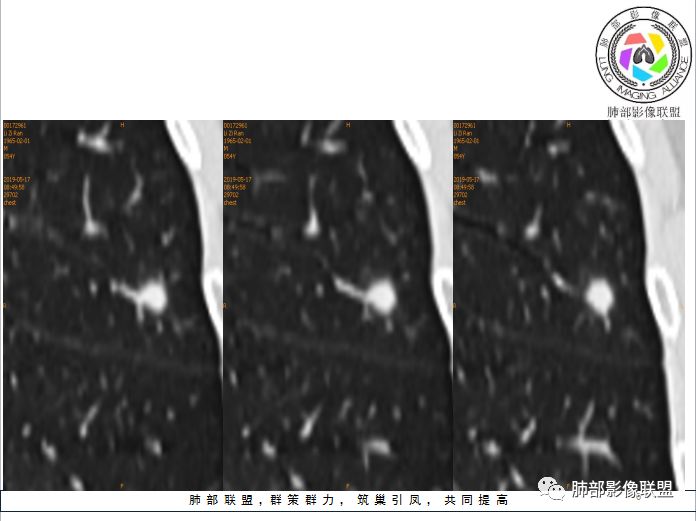

孤立结节型隐球菌影像表现:

划重点:1、胸膜下、两下肺多见。

2、“3个1/3”:1/3与胸膜相连,1/3内部可见空泡征,1/3有晕征

3、“2个2/3”:2/3与胸膜有间隙,2/3近段与血管相连。

1、与炎性假瘤、恶性肿瘤鉴别:恶性肿瘤边缘膨隆,收缩也是毛毛糙糙的,炎性假瘤收缩力较强,边缘凹陷的多。隐球菌孤立结节收缩力弱,膨胀力也弱,与胸膜关系多为糊墙,部分有间隙。右边两幅可以看到胸膜增厚,胸膜下脂肪间隙增宽。晕中长毛刺,边缘平直,血管走行自然,鉴别肺癌。